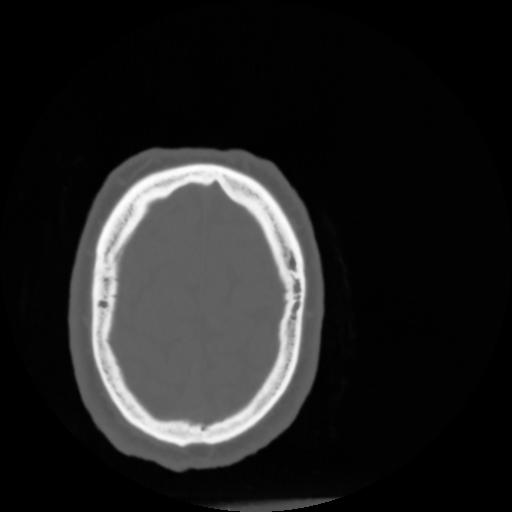

4 CEREBRO,,Vol,0.5,CEREBRO,,